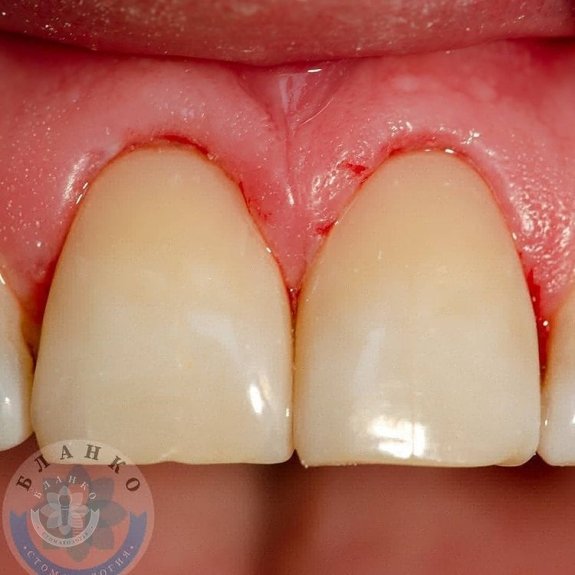

💎2 фото – на етапі лікування (препарування з вестибулярної та піднебінної поверхні).